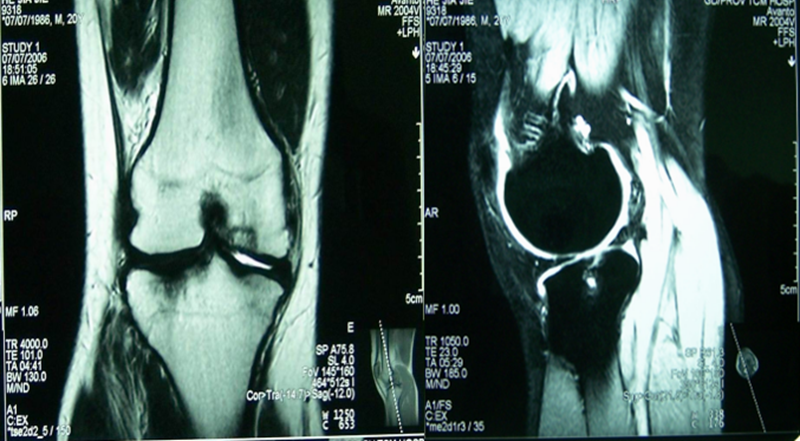

病例2:男性,19岁,因发现右膝关节内翻、过伸畸形伴跛行5年(左侧膝关节也有类似畸形,暂时无症状)。于2006年7月就诊,其母亲也有类似病史。查体:右膝关节内翻畸形约15度,应力下过伸约20度,内翻及外翻时膝关节均有松动感,Lanchman试验(+)。无负重下X片示:右膝关节内翻畸形约15度,胫骨平台无后倾,倒呈前倾13º。膝关节MR示:右膝内侧股骨及胫骨软骨面已有缺损并囊性变。诊断:先天性膝关节内翻畸形(Blount病)。

术前膝关节MR示:右膝内侧胫、股骨骨软骨面已有缺损并囊性变